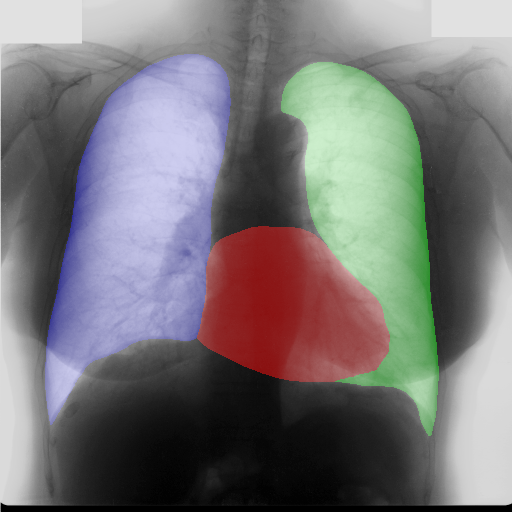

Moreover, in order to clarify the limits of the three–stage method, we assessed the quality of the segmentation results based on three human experts, who were asked to check 20 chest X–ray images, along with the corresponding supervision and the segmentation obtained by the SMANET network. Such images were chosen among those that can be considered difficult, at least based on the high error obtained by the segmentation algorithm. Figure 7 and Figure 8 show different examples of the images evaluated by the experts. The first column represents the chest X–ray image, while the second and the third columns, whose order was randomly exchanged during the presentation to the experts, represent the target segmentation and our prediction, respectively. The three physicians were asked to choose the best segmentation and to comment about their choice. Apart from a general agreement of all the doctors on the good quality of both the target segmentation and the segmentation provided by the three–stage method, surprisingly, they often chose the second one. For the examples in Figure 7, for instance, all the experts share the same opinion, preferring the segmentation obtained by the SMANET over the ground–truth segmentation. To report the results of the qualitative analysis, we numbered the target and predicted segmentation with 1 and 2, respectively, while doctors were assigned unordered pairs to obtain an unbiased result. Then, with respect to Figure 7(a), the comments reported by the experts were: 1) In segmentation 1, a fairly large part of the upper left ventricle is missing; 2) I choose the segmentation number 2 because the heart profile does not protrude to the left of the spine profile; 3) The best is No. 2, the other leaves out a piece of the left free edge of the heart, in the cranial area. Instead, for Figure 7(b), we obtained: 1) The second image is the best for the cardiac profile. For lung profiles, the second image is always better. The only flaw is that it leaks a bit on the right and left costophrenic sinuses. 2) Image 2 is the best, because the lower cardiac margin is lying down and does not protrude from the diaphragmatic dome. Image number 1 has a too flattened profile of the superior cardiac margin. 3) No. 2 for the cardiac profile more faithful to the real contours.

Instead, they reported conflicting opinions or decided not to give a preference with respect to the examples in Figure 8. When they agreed, they generally found different reasons for choosing one segmentation over the other. With respect to Figure 8(a) the comments reported by the experts were: 1) I prefer not to indicate any options because the heart image is completely subverted; 2) Segmentation number 2 is better, even if it is complicated to read because there is a “bottle–shaped” heart. The only thing that can be improved in image 2 is that a small portion of the right side of the heart is lost; 3) No. 1 respects more what could be the real contours of the heart image. Instead, for Figure 8(b) we obtained: 1) I prefer No. 2 because the tip of the heart is well placed on the diaphragm and does not let us see that small wedge–shaped image that incorrectly insinuates itself between heart and diaphragm in image 1 and which has no correspondence in the RX; 2) Both are good segmentations. Both have small problems, for example: in segmentation 1 a small portion of the tip (bottom right of the image) of the heart is missing, in segmentation 2 a part of the outflow cone (the “upper” part of the heart) is missing. It is difficult to choose, probably better No. 1 because of the heart; 3) No. 2 because No. 1 carnally probably exceeds the real dimensions of the cardiac image, including part of the other mediastinal structures.

These different evaluations, albeit limited by the small number of examined images, confirm the difficulty of segmenting CXRs, a difficulty that is likely to be more evident in the case of the images selected for our quality analysis, which were chosen based on the large error produced by the segmentation algorithm.